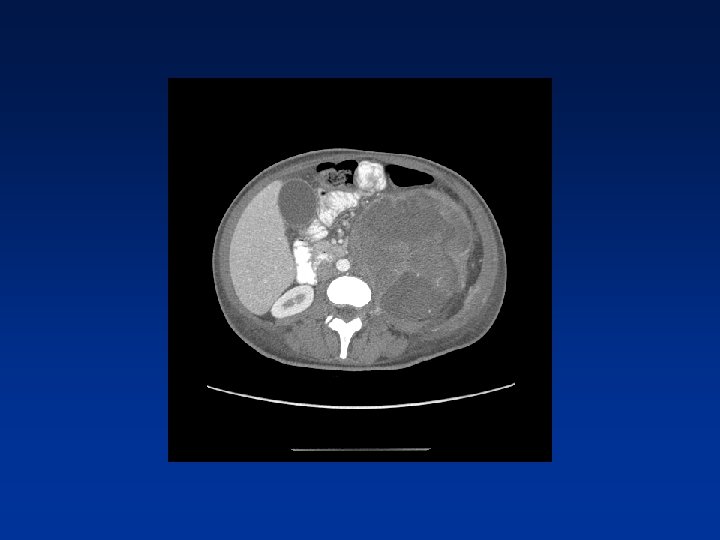

CASE